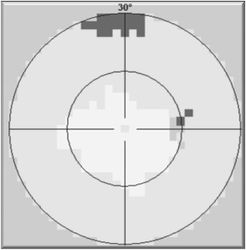

Vyšetření statickým počítačovým perimetrem - zorné pole před

Vyšetření statickým počítačovým perimetrem - zorné pole po